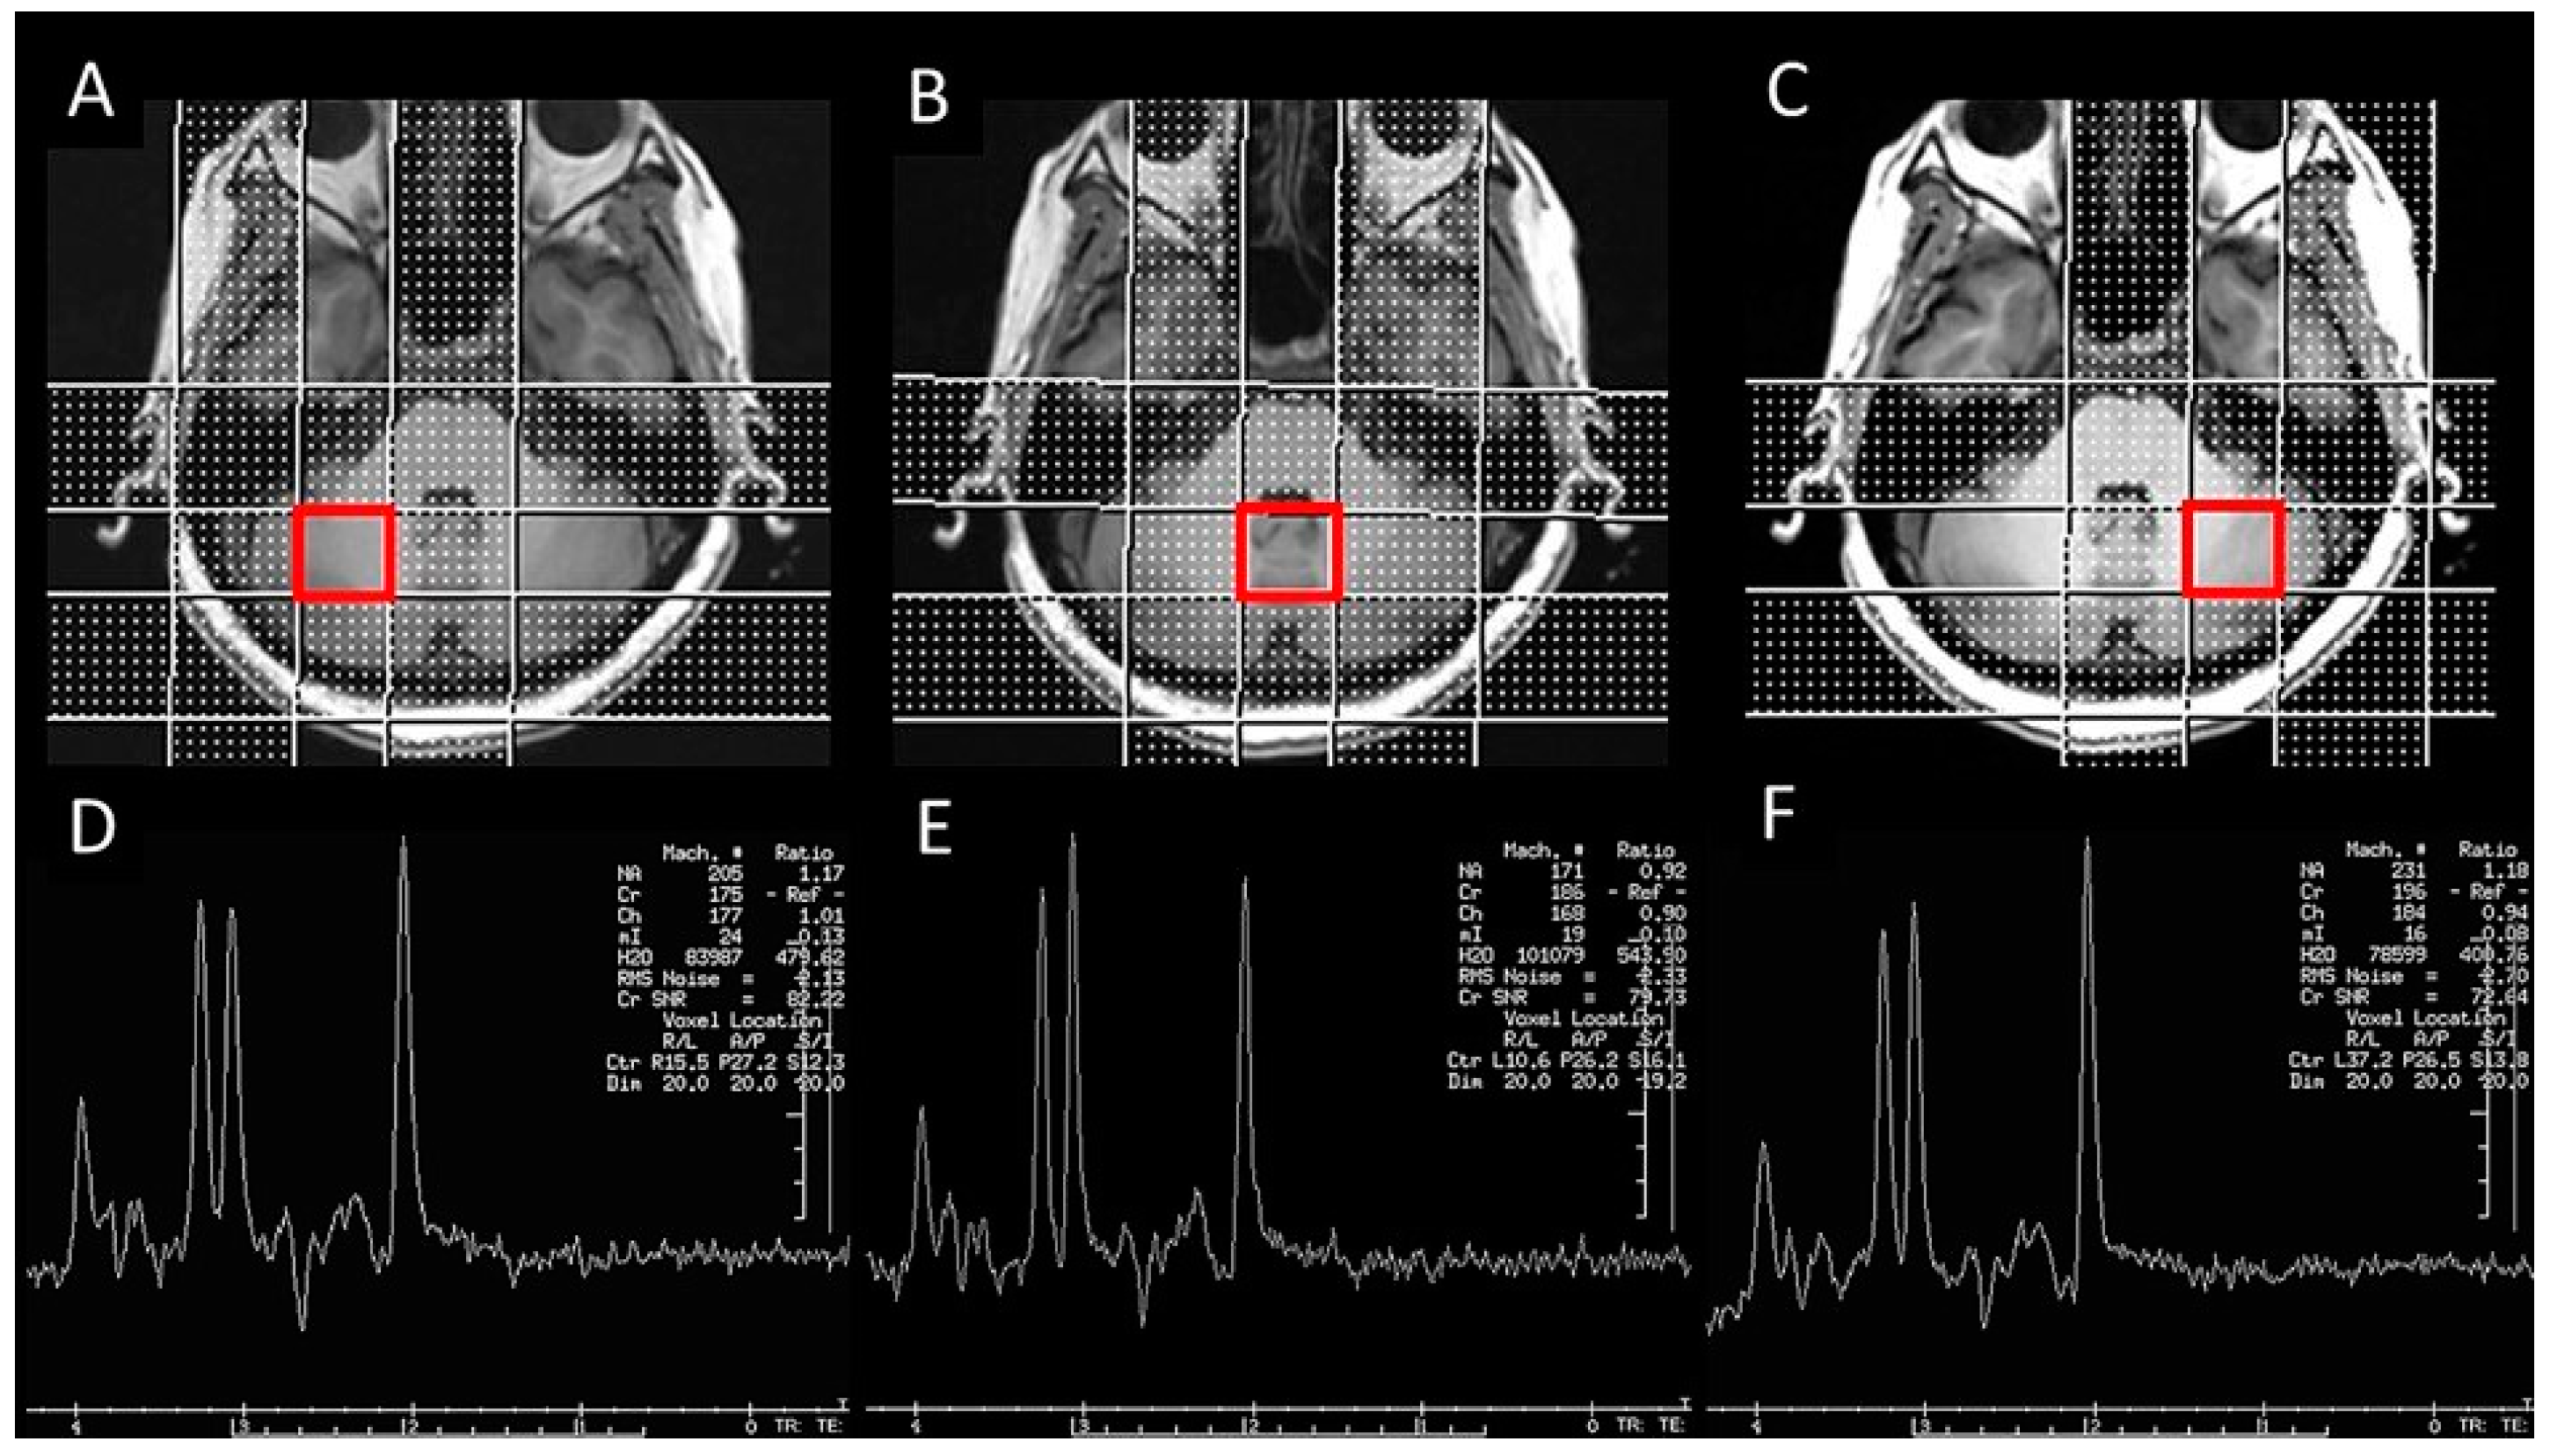

Imaging was performed using a 3T (Discovery MR750; GE Healthcare, WI, USA) MRI scanner with an 8-channel head coil. High-resolution T1-weighted cerebellar structural images were acquired using a 3D fast spoiled gradient-echo sequence (BRAVO), with the following parameters: repetition time (TR) = 8.2 ms, echo time (TE) = 3.2 ms, inversion time (TI) = 450 ms, flip angle = 12°, field of view = 256 mm, 172 slices, resolution = 1 × 1 × 1 mm3, and axial acquisition. Cerebellar MRS data were acquired using a volume-selective, inversion-recovery, water-suppressed, spectroscopy sequence (PROBE), with the following parameters: TR = 1500 ms, TE = 144 ms, spectral bandwidth = 2000 Hz, sampling resolution = 20 × 20 × 20 mm3, and number of excitations = 128. Prior to each acquisition, automatic shimming and water suppression were performed. Three voxels of interest were positioned, each in the right cerebellar hemisphere, left cerebellar hemisphere, and cerebellar vermis (Figure 1).

Figure 1.

A representative schematic of cerebellar ROIs for MR spectroscopy. (A–C) Right cerebellar hemisphere, cerebellar vermis, and left cerebellar hemisphere ROIs. (D–F) Corresponding spectra for each ROI.